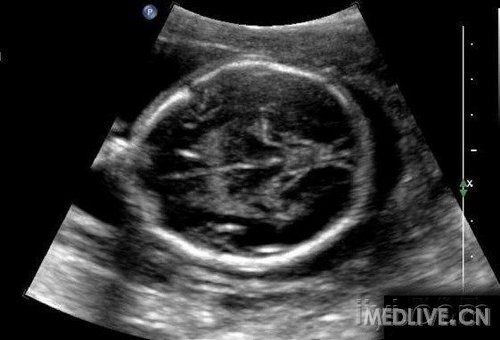

8.孕13-27周均属于中期妊娠。在此期间可以检测胎儿的生长发育情况,了解胎儿构造及羊水胎盘情况。

c.心脏